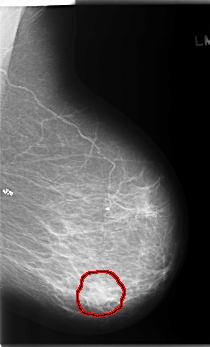

C_0204_1.RIGHT_CC

LEFT_CC LINES 5936 PIXELS_PER_LINE 3576 BITS_PER_PIXEL 12 RESOLUTION 50 OVERLAY

FILE: C_0204_1.LEFT_CC.OVERLAY

TOTAL_ABNORMALITIES 1

ABNORMALITY 1

LESION_TYPE MASS SHAPE LOBULATED MARGINS MICROLOBULATED

ASSESSMENT 5

SUBTLETY 5

PATHOLOGY MALIGNANT

TOTAL_OUTLINES 1

BOUNDARY